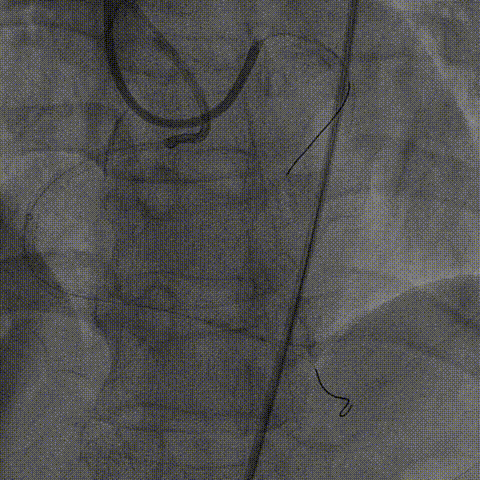

2、正向介入器械:Finecross微导管(130cm);XT-A导丝尝试寻找闭塞段入口及微通道,UB3尝试进入远段真腔失败,保留正向导丝启动逆向介入治疗。

右冠PCI

逆向器械:

1、选择近段粗大间隔支;Finecross(150cm);Sion导丝surfing通过侧枝循环至右冠远段,跟进微导管后尝试UB3、Gaia3导丝至闭塞段远段与正向导丝重叠,但闭塞段钙化可能导丝逆向导丝无法进一步前进突破。

策略转换:

1、逆向导丝无法进一步前进突破后及时转换策略,决定以逆向导丝为路标,操控正向导丝定向穿刺逆向导丝。

2、正向升级为Gaia3导丝多投照体位穿刺并靠近逆向导丝,但无法进入远端真腔,升级为Pilot200导丝试图尽量考虑血管真腔加强支撑力后启动Reverse-Cart,多体位操控后导丝幸运进入血管远端真腔。